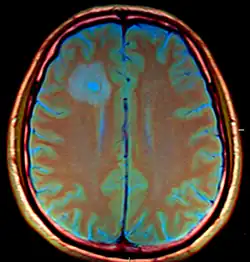

| Brain abscess in a person with a CSF shunt. The abscess is the darker gray region in the lower left of the image (corresponding to the right parietal lobe). The lateral ventricles are visible in black in the center of the brain, adjacent to the abscess.[1] | |